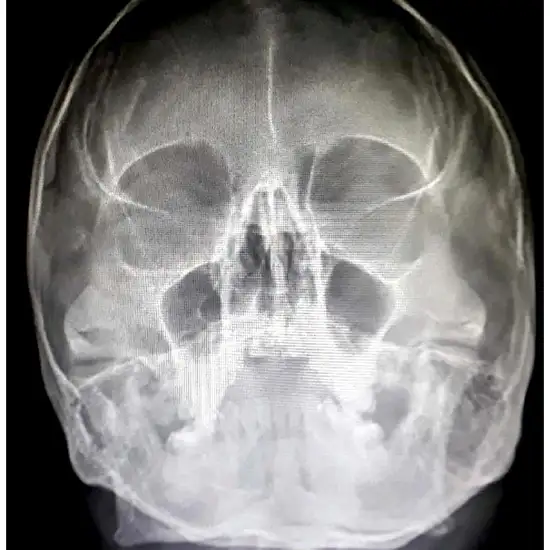

PNS X-Ray (Paranasal Sinus) The AP lateral view is sometimes referred to as a sinus X-ray. It is an imaging test that employs a small quantity of radiation at an angle to the chin. It is used to gather diagnostic information about the bony structures at the front of the skull, particularly the frontal and maxillary sinuses. The test is used to diagnose sinusitis, often caused by a bacterial infection that develops after a viral illness.

• To detect sinus infection and inflammation (chronic sinusitis).

• To diagnose sinus fractures

• To identify paranasal sinus birth abnormalities or abnormal development.